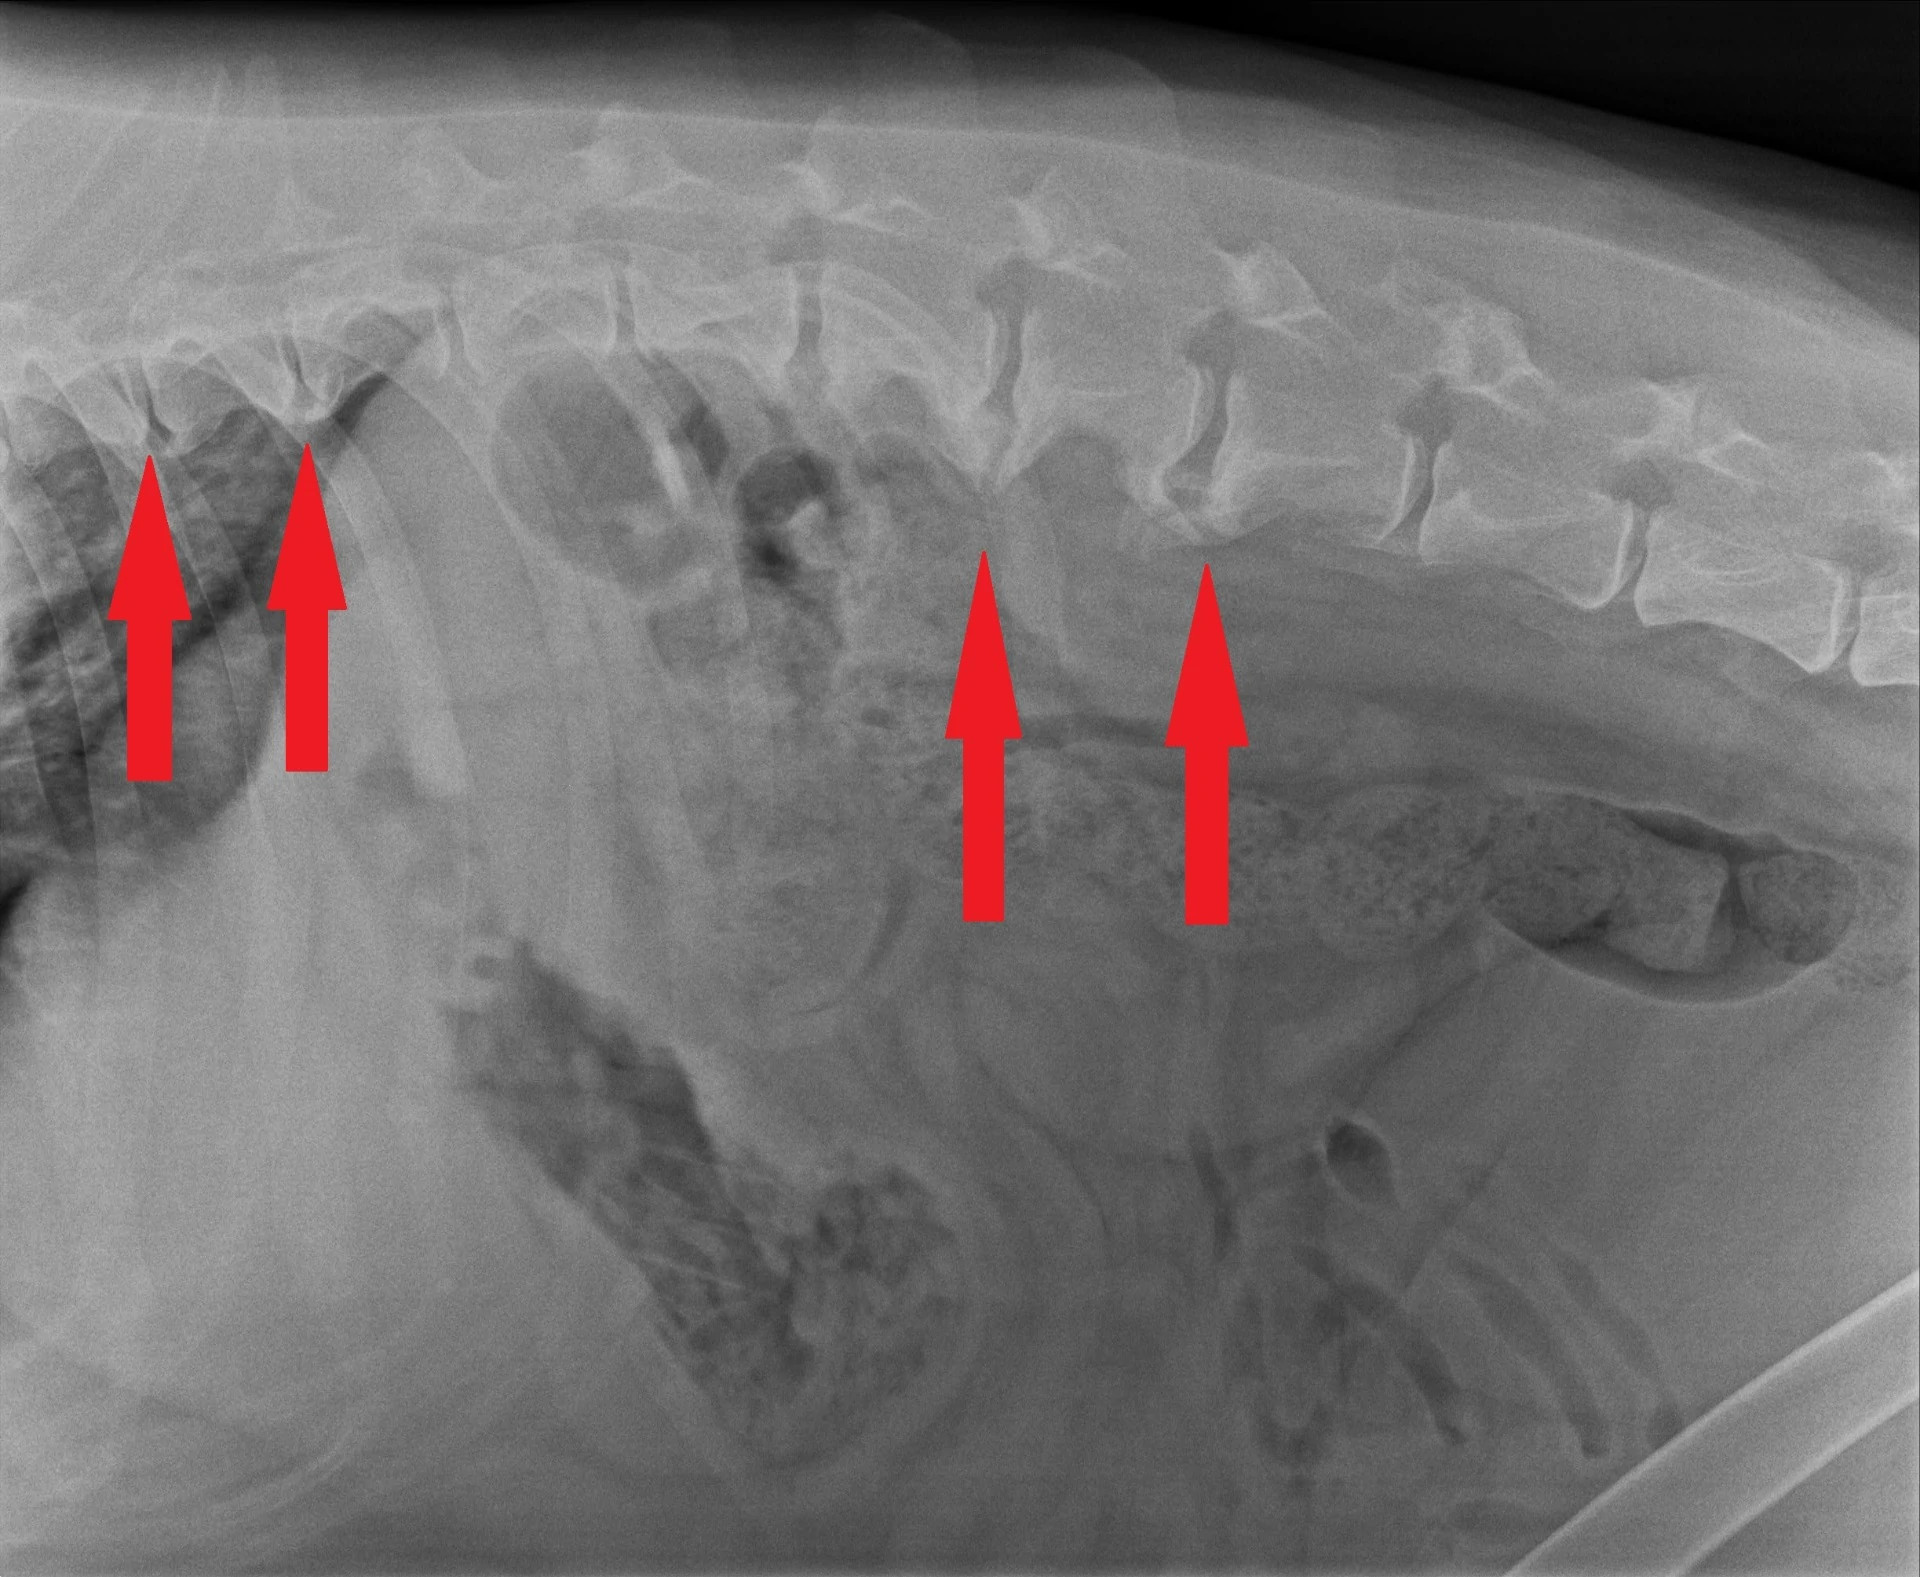

Ze začátku je většina postižených psů bez příznaků, ale postupem času, jak se kostní výrůstky na páteři zvětšují, začínají způsobovat bolestivost a sníženou pohyblivost páteře, nebo mohou způsobit dráždění kořenových nervů vycházejících z meziobratlové oblasti a způsobit výraznější bolest i kulhání. Spondylóza sama o sobě nicméně nezpůsobuje paretické stavy, pokud u psa dojde k paréze/plegii, je třeba další diagnostiky. Diagnostika spondylózy probíhá u veterinárního lékaře a ten diagnózu vyhodnocuje z RTG snímků páteře. K vyhotovení snímků pro diagnostiku spondylózy obvykle není třeba uvádět psy do anestezie.

Je nutno podotknout, že související možné problémy s meziobratlovými plotýnkami už z RTG snímků není možné zdiagnostikovat.